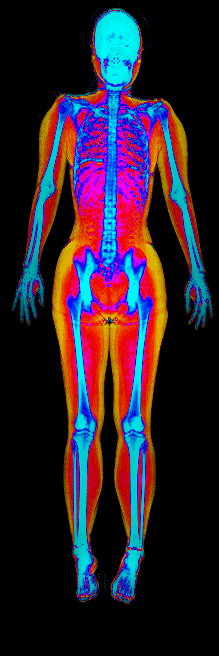

This page features real, anonymized DEXA scan images from BodyStats clients, organized by gender and body fat percentage in 5% increments. DEXA (Dual-Energy X-ray Absorptiometry) is the clinical gold standard for measuring body composition — far more accurate than scales, calipers, or visual estimates.

Each colorized scan shows the distribution of fat tissue (shown in warmer colors) and lean tissue (cooler colors) throughout the body. Compare your own DEXA scan to others in your range, or see what different body fat levels actually look like on a scan.

Female DEXA Scans by Body Fat %

15 to 20% body fat